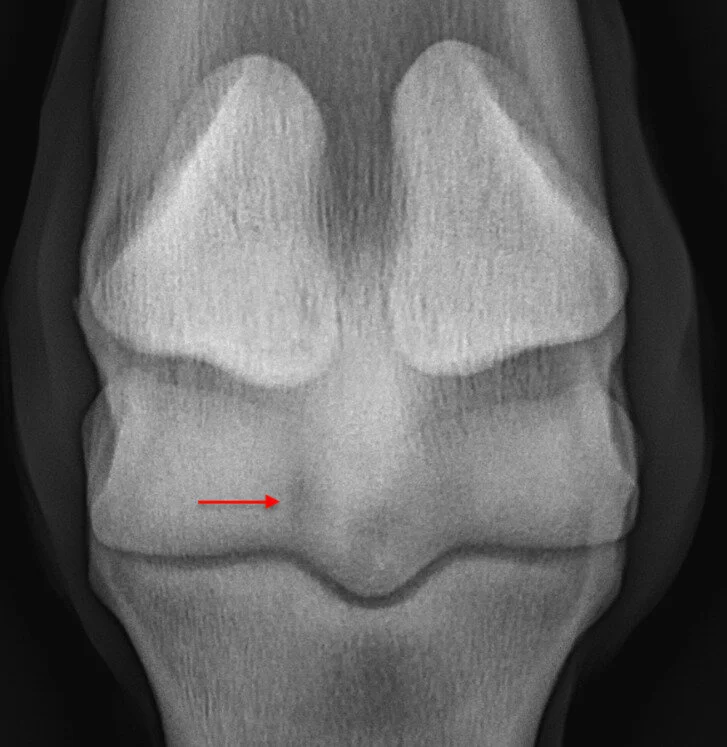

From www.researchgate.net

Lateromedial radiograph of the fetlock demonstrating a bone Horse Bone Spur Fetlock palmar osteochondral disease of the fetlock affects the subchondral bone of the palmar/plantar aspects of the distal. Countering the high load experienced by the joint is the. The fetlock joint acts as a shock absorber and allows for fluid movement. complications of long pastern bone fractures include poor alignment at the fracture site, failure of implants (such as.. Horse Bone Spur Fetlock.